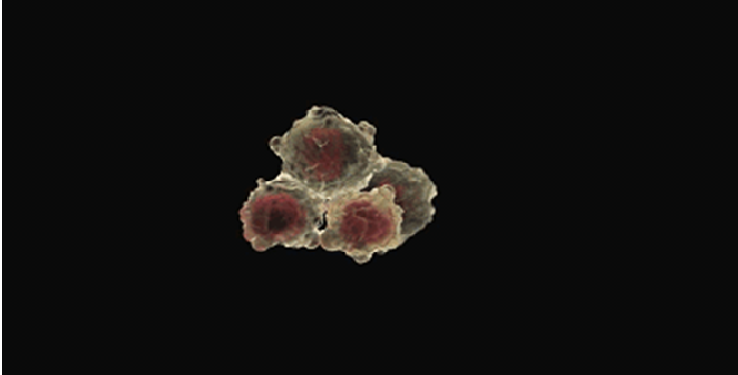

Sở dĩ tuyên bố này gây ra làn sóng dư luận là bởi con số này dường như nằm ngoài tầm với của loài người. Thế nhưng Tiến sĩ Aubrey de Grey đã đưa ra dẫn chứng về tế bào bất tử Hela. Theo ông, tiền đề của quá trình lão hóa của con người là do tế bào chết đi sau khoảng 56 lần phân chia. Tuy nhiên, tế bào Hela khác với tế bào bình thường của con người bởi nó chính là tế bào bất tử.

Tế bào này tình cờ được tạo ra bởi George Otto Gey, một nhà khoa học tại bệnh viện Johns Hopkins, Maryland, Mỹ vào năm 1951. Ông lấy mẫu từ một người phụ nữ da đen mắc bệnh ung thư tên là Henrietta Lacks. Sau đó, các nhà khoa học đã đặt tên cho tế bào là Hela và nó nhanh chóng trở thành mẫu vật vô giá với y khoa toàn cầu.

Khác với các tế bào người bình thường, tế bào Hela có thể tồn tại và sinh sản bình thường trong phòng thí nghiệm. Các nhà khoa học đã sử dụng chúng trong nghiên cứu vắc xin bại liệt, thử nghiệm trong môi trường không trọng lực, nhân bản, tạo bản đồ gen và nuôi cấy mô.

Với giới y học, việc sở hữu tế bào bất tử là vô cùng quan trọng trong nghiên cứu. Cho đến nay, ngoài tế bào Hela, chưa ai tìm ra tế bào bất tử nào khác. Kể từ sau khi bước sang thế kỷ 21 tới nay, đã có 5 công trình nghiên cứu dựa trên tế bào Hela đoạt giải Nobel. Và tiến sĩ Aubrey de Grey cho rằng nếu khám phá được bí mật của tế bào Hela, con người có thể sống tới 1.000 tuổi.